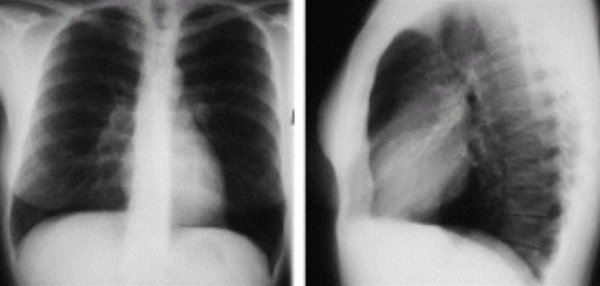

Thorax, røntgen, normal

Røntgen af thorax, front/side, normal.